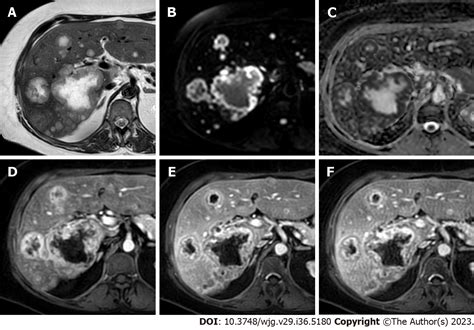

MRI with Contrast Highly sensitive; often used to differentiate benign lesions from metastases.

PET Scan Used to detect metabolic activity and assess for widespread disease.

Abdominal CT Scan Provides detailed cross-sectional images to identify lesion size and location.